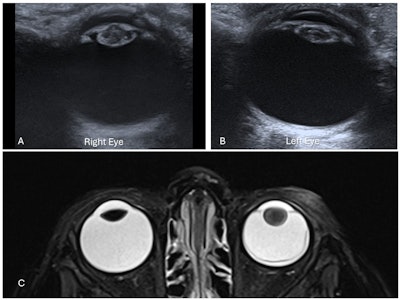

Bilateral congenital cataracts in a 15-day-old infant. Axial ultrasound images of the right lens (A) and left lens (B) demonstrate increased thickness with intralenticular echoes and increased echogenicity of both the anterior and posterior lens walls. (C) Left cataract in a different 2-year-old child with left retinoblastoma. Axial T2-weighted fat-saturated (T2W FS) MRI of the orbits shows globular thickening of the left lens with increased T2 signal compared to the normal right lens, consistent with cataract formation. Additional findings include left retinal detachment and mucosal thickening of the bilateral ethmoid air cells. Attachment of the retinal membrane to the optic disc is not visible in this image. All figures courtesy of Drs. Lasith Ihalagamage, Albert Prat Matifoll, Robert Goetti, and Kristina Prelog and presented at RANZCR's 2025 ASM.